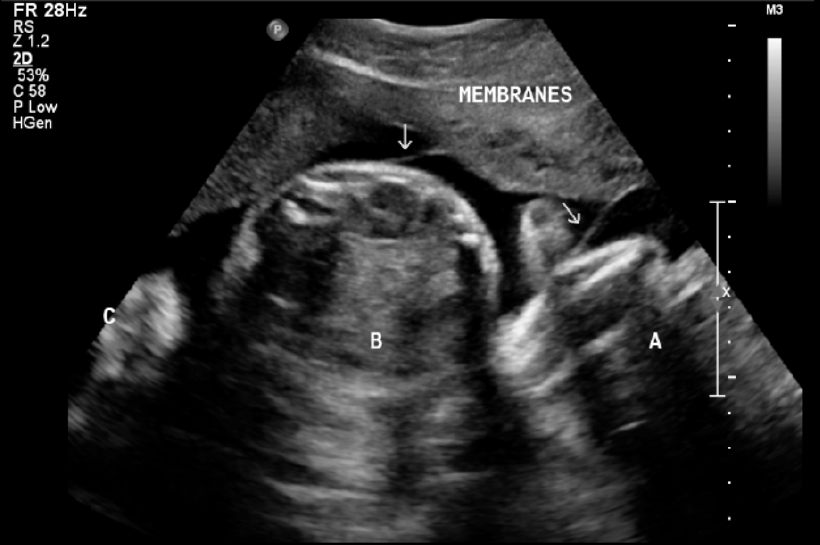

The patient had a natural conception which ended in a complete miscarriage at six week gestation followed by an unsuccessful in vitro fertilization (IVF) attempt during her assessment period. A second IVF cycle (with donor eggs) was successful with a triplet (triamniotic trichorionic) pregnancy (Figure 1). Her antenatal profile was essentially normal as follows: hemoglobin 12.5 g/dl, hepatitis-B surface antigen (HBsAg) negative; HIV negative; venereal disease research laboratory (VDRL) Negative with blood group O and positive Rhesus factor. The anomaly ultrasound scan done at 21st week detected no fetal anomalies. A subsequent growth scan at 27 weeks gestation revealed normal growth in all three fetuses.

Figure 1: Ultrasound showing the three fetuses (fetus A, B and C) in different amniotic sacs as shown by the arrows.